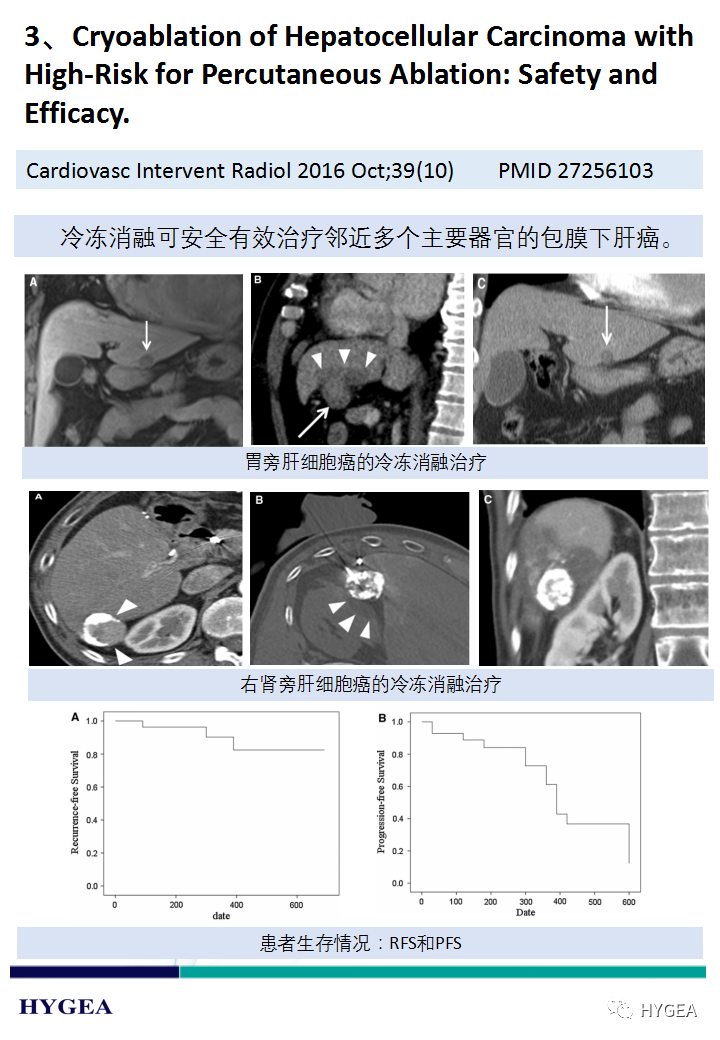

【海杰亚科研资讯】第188期——冷冻消融肝癌专题